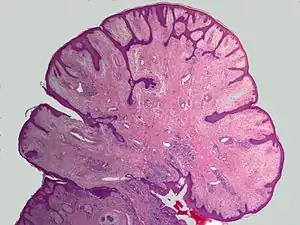

Angiofibroma (AGF) is a descriptive term for a wide range of benign skin or mucous membrane (i.e. the outer membrane lining body cavities such as the mouth and nose) lesions in which individuals have: 1) benign papules, i.e. pinhead-sized elevations that lack visible evidence of containing fluid; 2) nodules, i.e. small firm lumps usually >0.1 cm in diameter; and/or 3) tumors, i.e. masses often regarded as ~0.8 cm or larger. AGF lesions share common macroscopic (i.e. gross) and microscopic appearances. Grossly, AGF lesions consist of multiple papules, one or more skin-colored to erythematous, dome-shaped nodules, or usually just a single tumor. Microscopically, they consist of spindle-shaped and stellate-shaped cells centered around dilated and thin-walled blood vessels in a background of coarse bundles of collagen (i.e. the main fibrous component of connective tissue).[1] Angiofibromas have been divided into different types but commonly a specific type was given multiple and very different names in different studies.[1] The following list gives a brief description of the AFG types and their alternate names.

Oral fibromas are also termed irritation fibromas, focal fibrous hyperplasia, and traumatic fibromas.[16] These lesions are nodules that occur on the buccal mucosa (i.e. mucous membranes lining the cheeks and back of the lips) or lateral tongue.[17] They may be irritating or asymptomatic and are the most common tumor-like lesions in the oral cavity. Oral fibromas are not neoplasms; they are hyperplastic (i.e. overgrowth) reactions of fibrous tissue to local trauma or chronic irritation.[18]